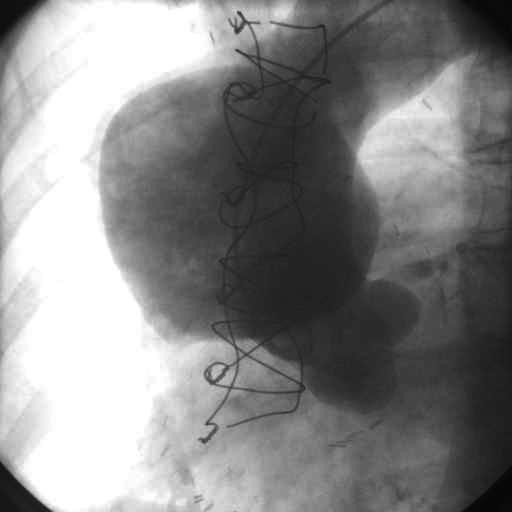

damar img 1

Crawford təsnifatı